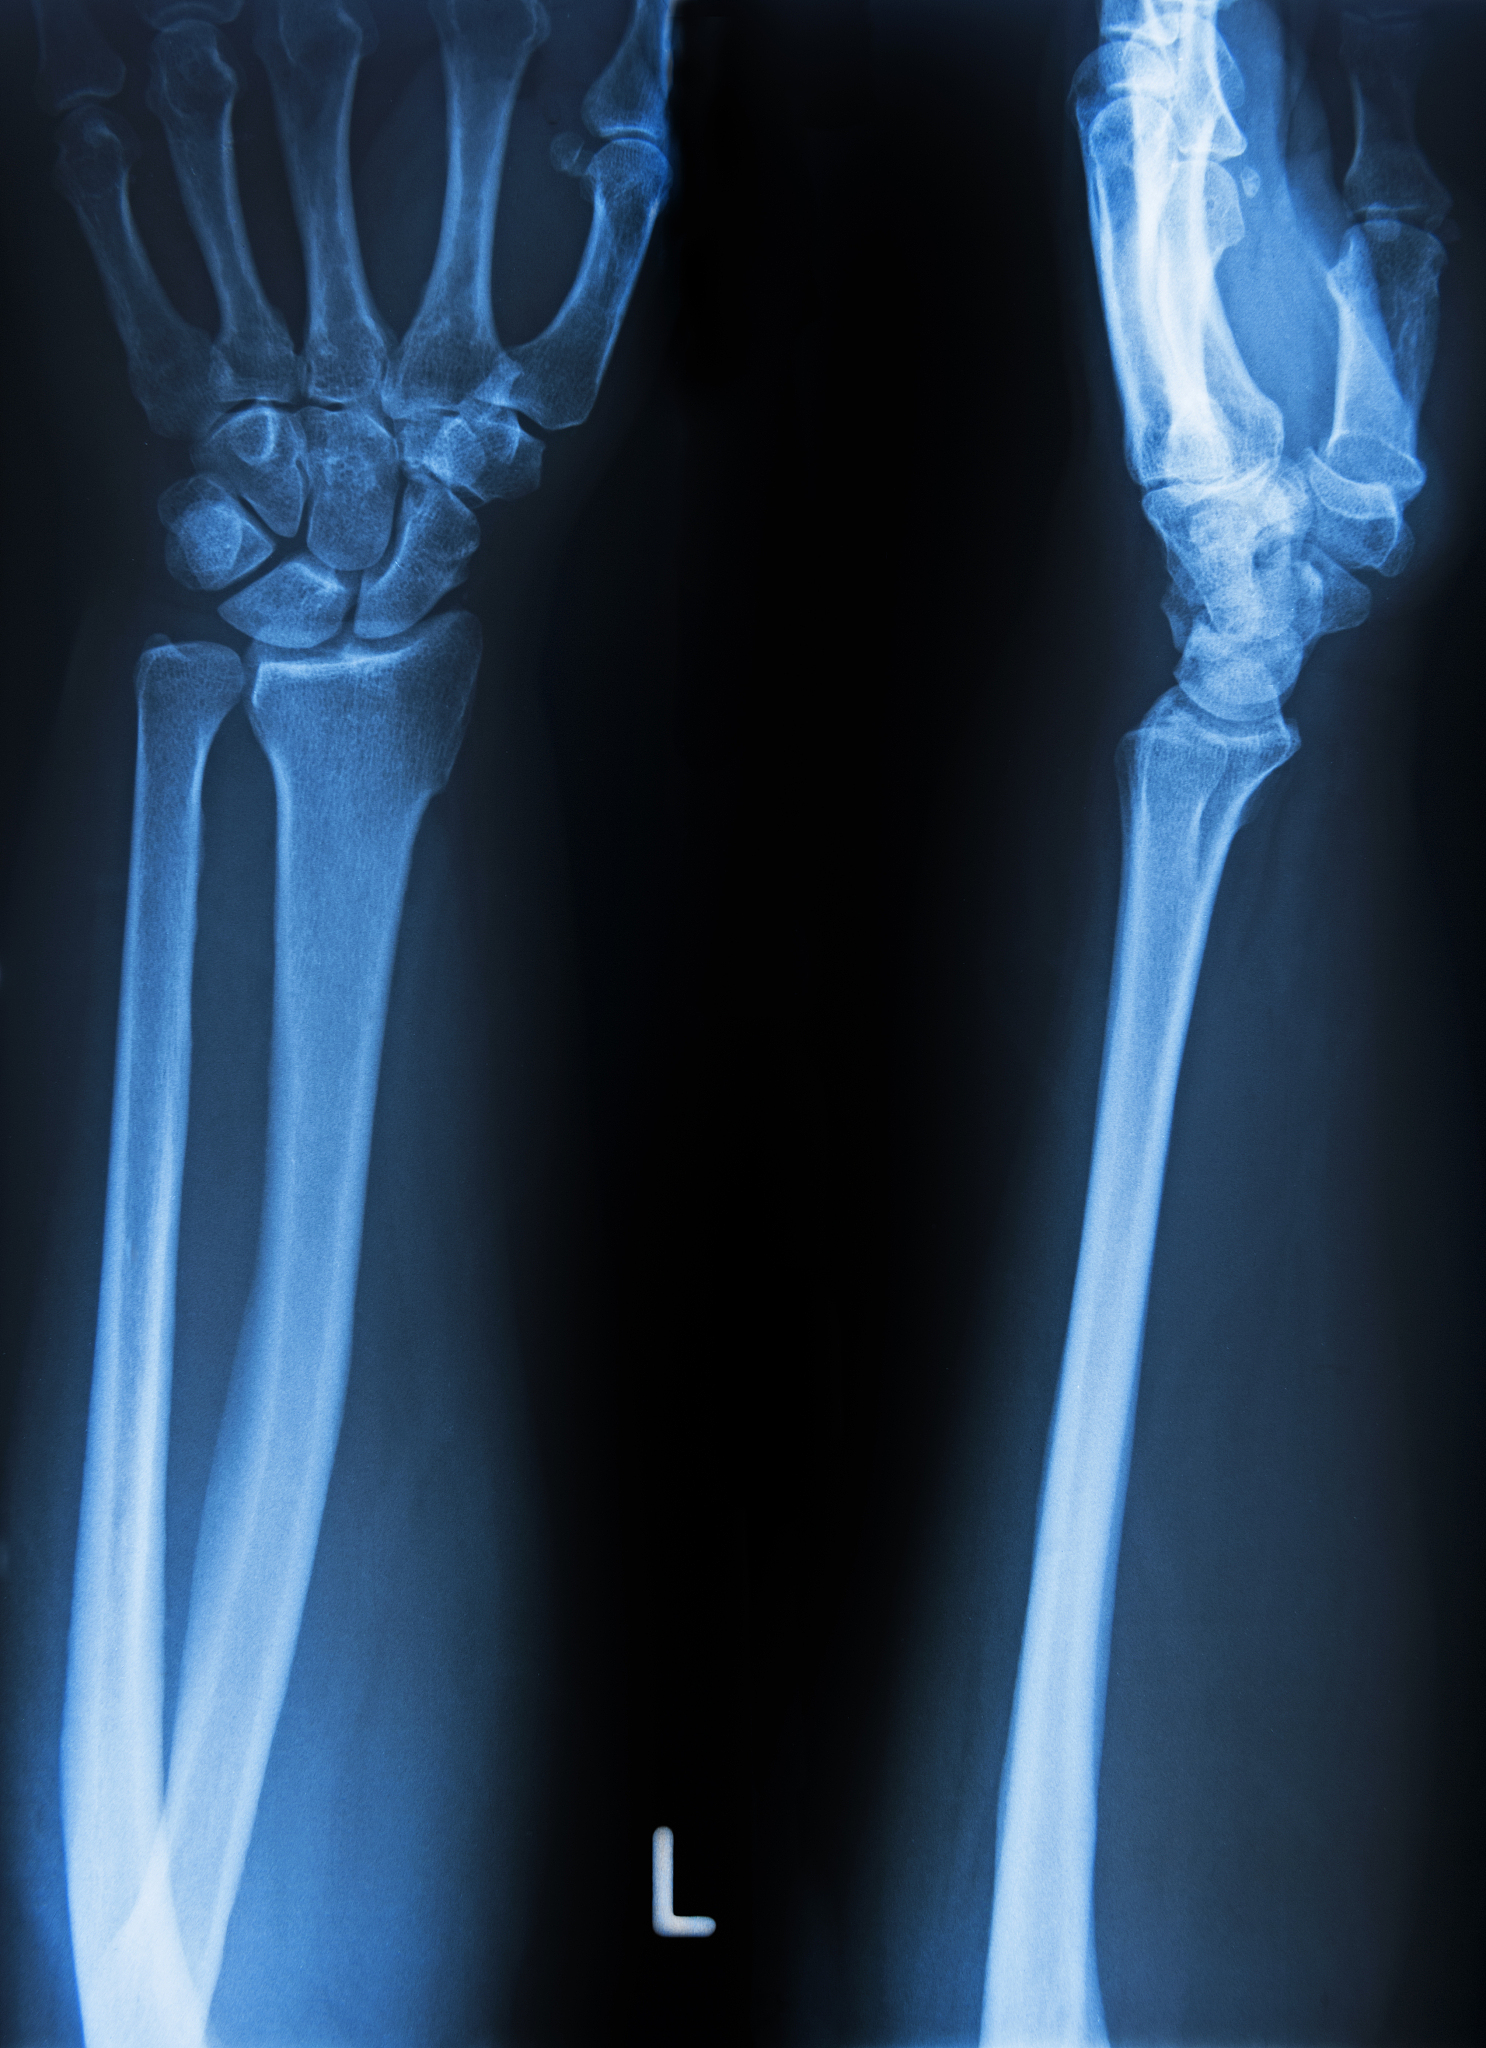

中级MCP关节,又称中央多关节关节,是指手指和脚趾中的关节,其中包括掌骨、桡骨和尺骨。它们之间的关系是,掌骨的一端连接到桡骨的一端,另一端连接到尺骨的一端,而尺骨的另一端连接到桡骨的另一端。中级MCP关节允许手指和脚趾弯曲和伸展,这在日常活动中非常重要。